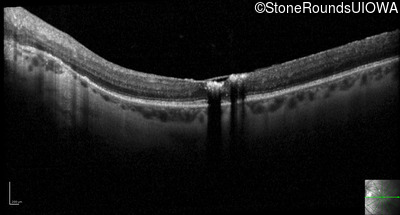

Optical Coherence Tomography - Right - 20/25

Exemplar / OCT Stack